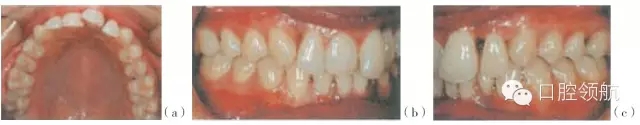

圖29.4 (a~c)有局限型侵襲性牙周炎病史的28歲的女性患者(不吸煙),之前進(jìn)行過(guò)牙周治療,左上中切牙及左下側(cè)切牙有炎癥。左下中切牙已有移位,不在牙弓的正?;【€(xiàn)內(nèi),出現(xiàn)傾斜及旋轉(zhuǎn)

圖29.5 (a,d)圖29.4患者的X線(xiàn)片,咬合面的X線(xiàn)片顯示上頜第一磨牙遠(yuǎn)中及下頜左側(cè)

第二磨牙,有齦下牙石和牙槽骨吸收。(b,c,e,f)根尖片顯示右上側(cè)切牙,左上中切

牙及側(cè)切牙,左下側(cè)切牙有齦下牙石及牙槽骨吸收